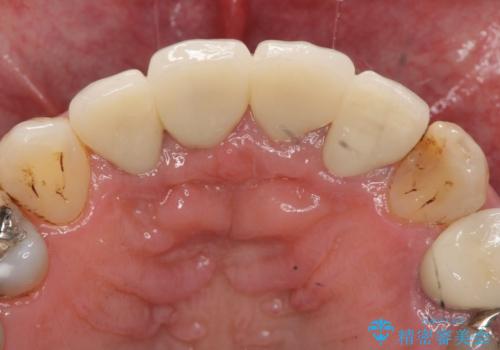

X線写真より問題のなかった根管治療は行わず、クラウンを除去し仮歯でを装着したのちジルコニアクラウンを製作していきます。

- 48.4万円(税込)(仮歯・ジルコニアクラウン×4)費用は治療当時の料金となります

失活歯の治療について

神経をすでに取られている歯の治療を行う場合、コアを除去したのちの再根管治療を行う場合とクラウンのみやり替えする場合、状況に応じて適切な治療をご提案いたします。